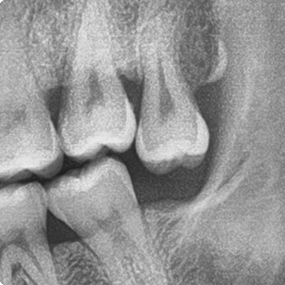

為了健保患者拔智齒的安全,遠離唇麻、舌麻、口鼻竇炎、大出血...等併發症,

☆本院特別巨資增設 ”千萬級3D AI透視電腦斷層”,並配合“成骨膠原蛋白”施作 (上述兩項目前健保無給付),讓您遠離神經傷害、口鼻竇(炎)相通...等併發症,除健保之外,難免會有避免併發症風險的自費項目,網路上經常會有看到智齒拔完後唇麻、舌麻、口鼻竇相通等併發症,在本院嚴格自我要求下,此類併發症在本院幾乎趨近於零。